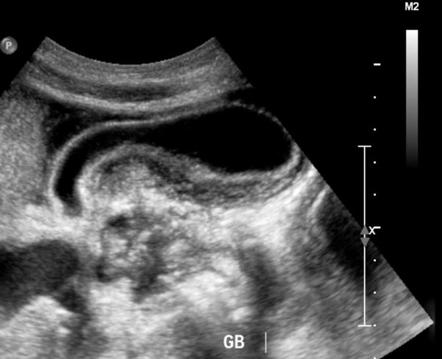

تحدث في 10٪ من حالات التهاب المرارة. التهاب حاد في المرارة في حالة #عدم وجود #حصوات في #المرارة. عادة ما يكون المرضى في حالة حرجة من مرض تصلب الشرايين في القلب ، أو الصدمة الحديثة ، أو الإصابة بالحروق ، أو الجراحة ، أو عدم استقرار الدورة الدموية.

قد يكون ظهور التهاب المرارة الشوكي الحاد خبيثًا ، ويتميز بحمى غير مفسرة ، أو زيادة عدد الكريات البيضاء ، أو فرط #أميلاز الدم ، أو ناقلات أمين غير طبيعية ، وغالبًا ما يفتقر المرضى إلى حنان الربع العلوي الأيمن.

يشمل التقييم التشخيصي التصوير بالموجات فوق الصوتية والتصوير المقطعي المحوسب وتصوير الأوعية الصفراوية.